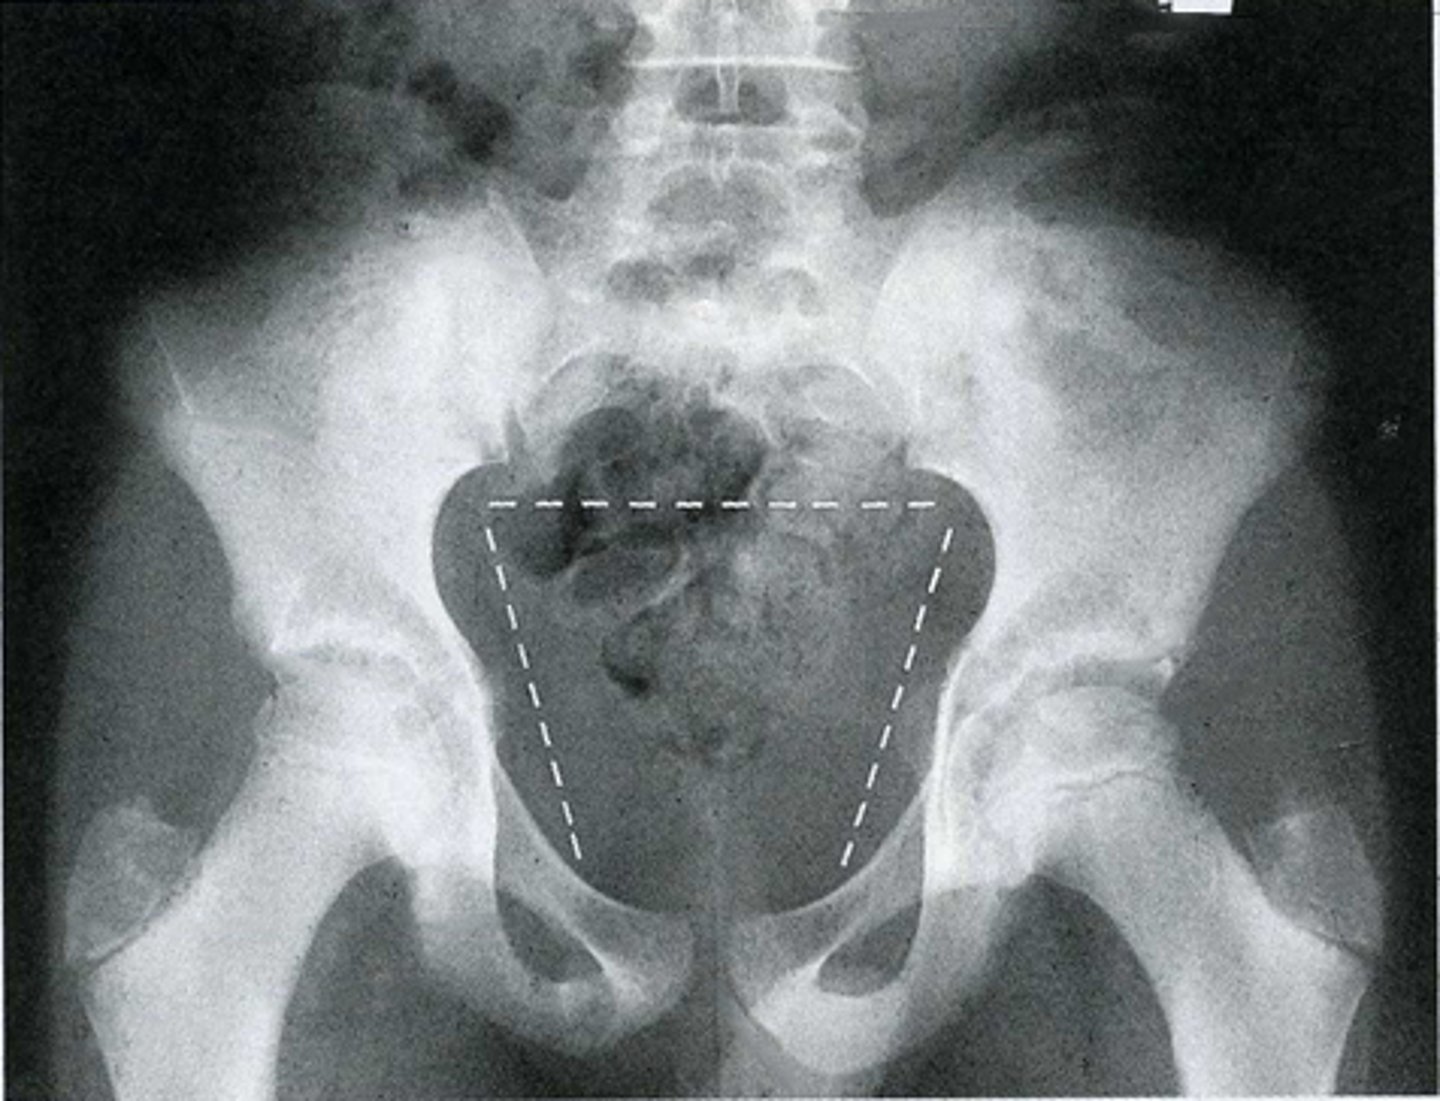

AP pelvis

What is the image?

16

L acetabulum

<p>What is indicated in the image?</p>

New cards

What is indicated in the image?

18

L ilium

20

L obturator foramen

22

L superior ramus of pubis

24

R anterior superior iliac spine (ASIS)

26

R ischial tuberosity

28

R sacroiliac joint

30

Sacrum